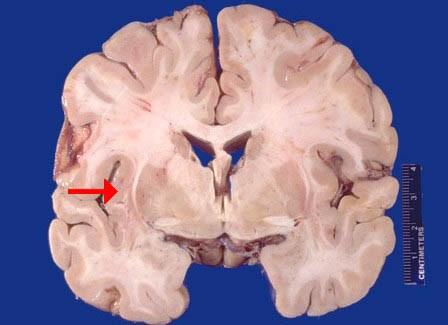

问题 如图箭头所示为大脑哪个部位 ( )

选项 A、岛叶 B、海马 C、颞叶 D、尾状核 E、壳核 一、单项选择题

答案 A